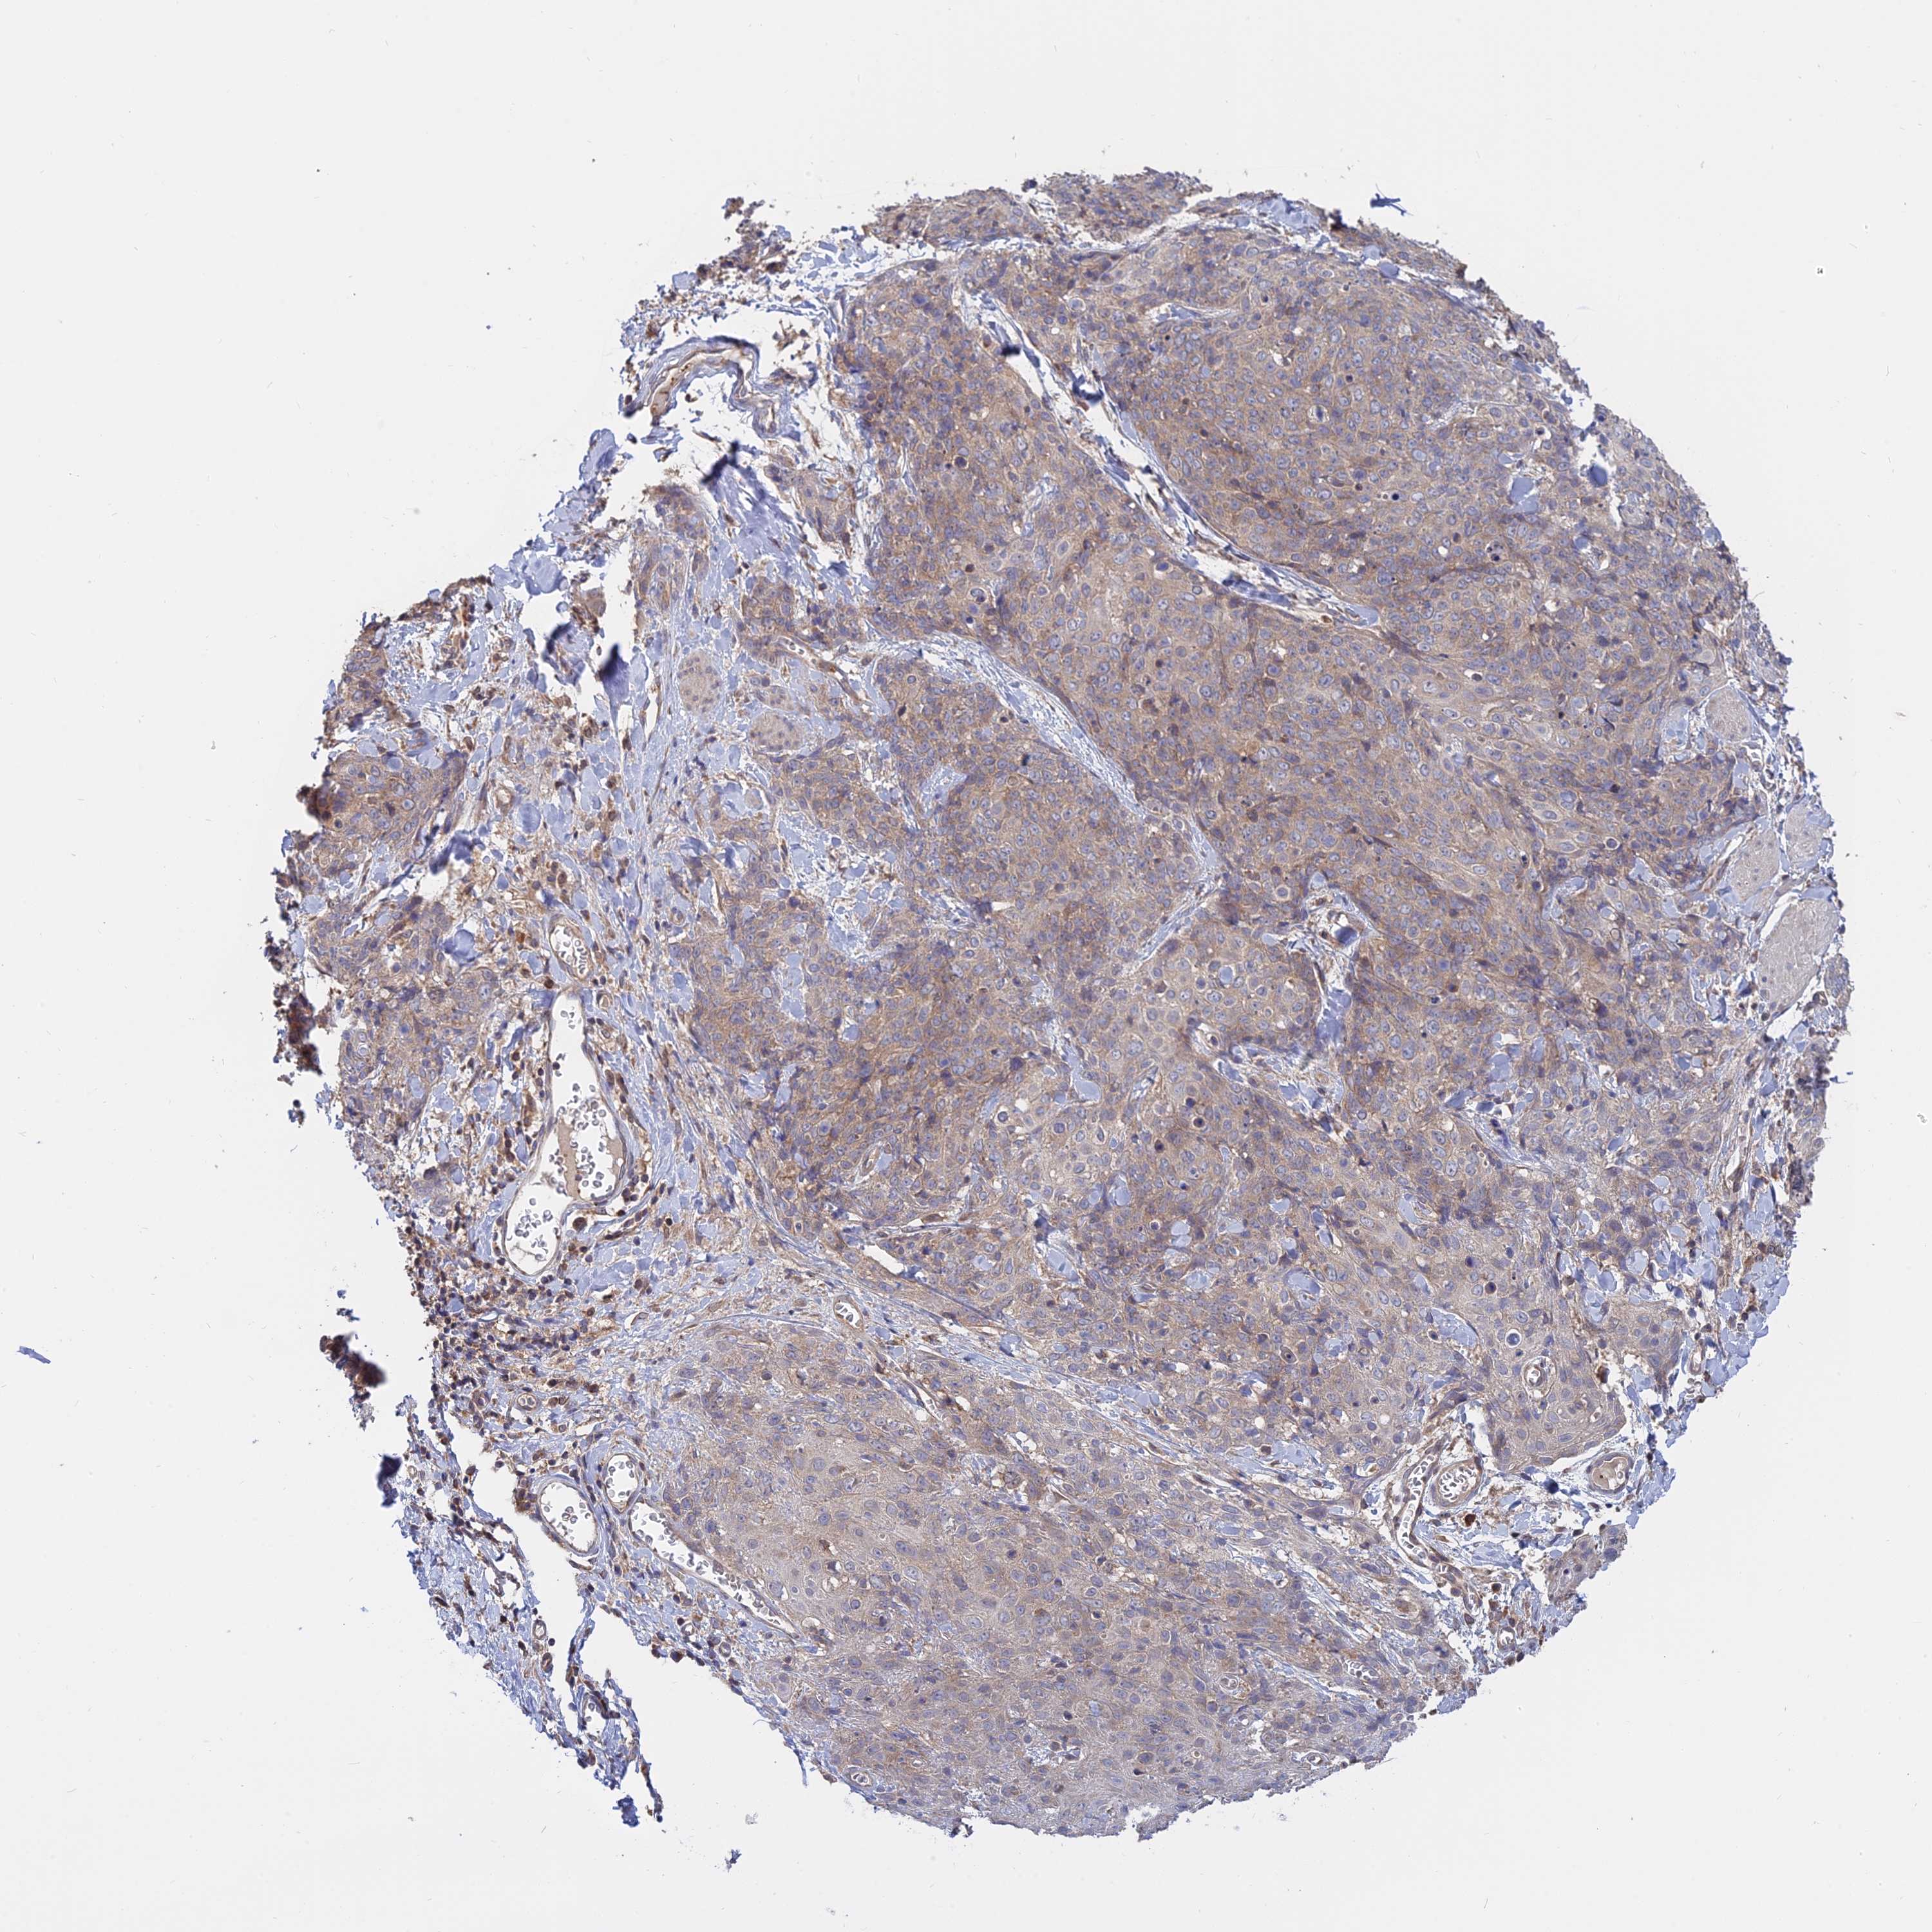

SKIN CANCER - Protein expressioni

A mouse-over function shows sample information and annotation data. Click on an image to view it in a full screen mode. Samples can be filtered based on level of antibody staining by selecting one or several of the following categories: high, medium, low and not detected. The assay and annotation is described here.

Antibody stainingi

Antibody staining in the annotated cell types in the current human tissue is reported as not detected, low, medium, or high, based on conventional immunohistochemistry profiling in selected tissues. This score is based on the combination of the staining intensity and fraction of stained cells.

Each image is clickable and will lead to virtual microscopy that enables deeper exploration of all samples and also displays staining intensity scores, fraction scores and subcellular localization as well as patient and tissue information for each sample.

Antibody HPA042296

Staining

High

Medium

Low

Not detected

Intensity

Strong

Moderate

Weak

Negative

Quantity

>75%

75%-25%

<25%

None

Location

Nuclear

Cytoplasmic/membranous

Cytoplasmic/membranous,nuclear

Basal cell carcinoma